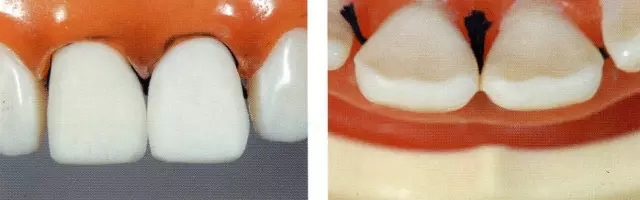

圖6 鄰接面和切緣的預(yù)備。避免傷到牙齦,要做排齦。如果遇到插不進(jìn)鄰接面的情況,可以在鄰接面預(yù)備好后再進(jìn)行插入。注意預(yù)備時(shí)不要磨到鄰接牙,把硅橡膠模型用在切緣上,這樣可以很好把握切削量。

圖4 開溝。在模型上形成0.5~0.7mm溝痕,再用筆標(biāo)記出來(lái)。在切緣上切削1.5mm使之成為butt joint。